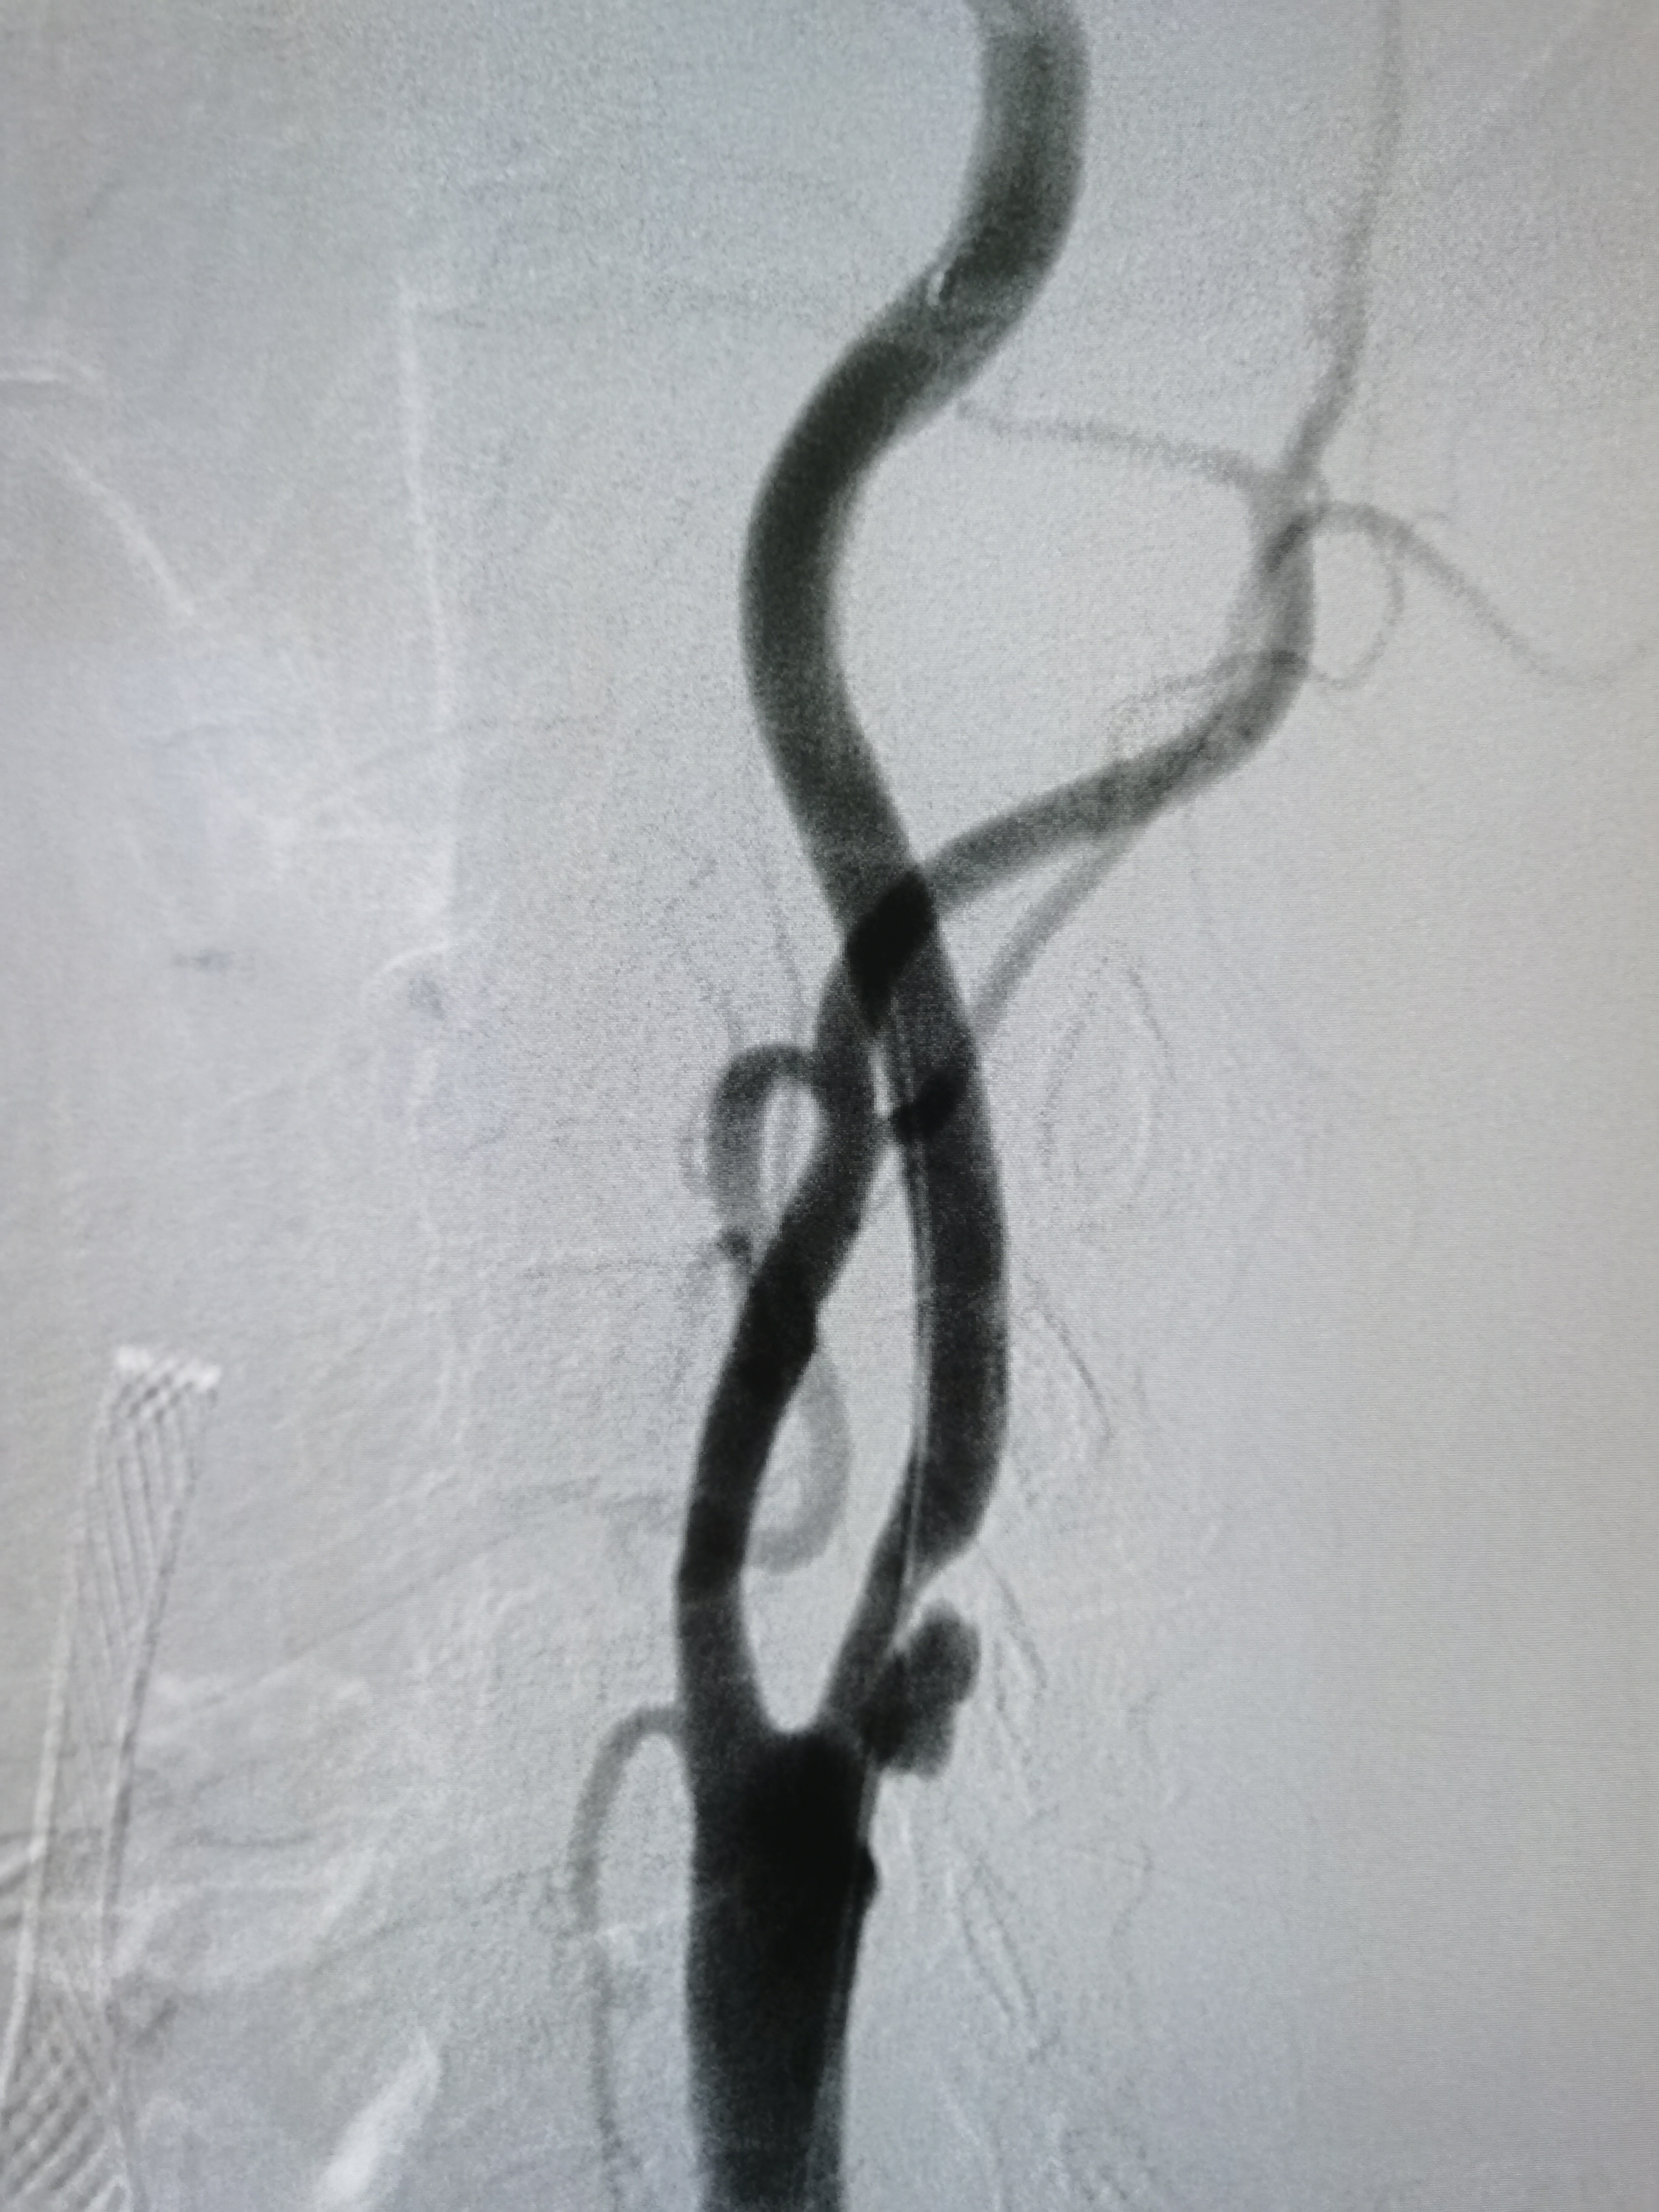

右侧颈内动脉起始部重度狭窄。

2/20,4/30球囊渐进性预扩后狭窄改善。

9/30支架定位后释放。

支架释放后狭窄解除。

支架释放后颅内血供改善。